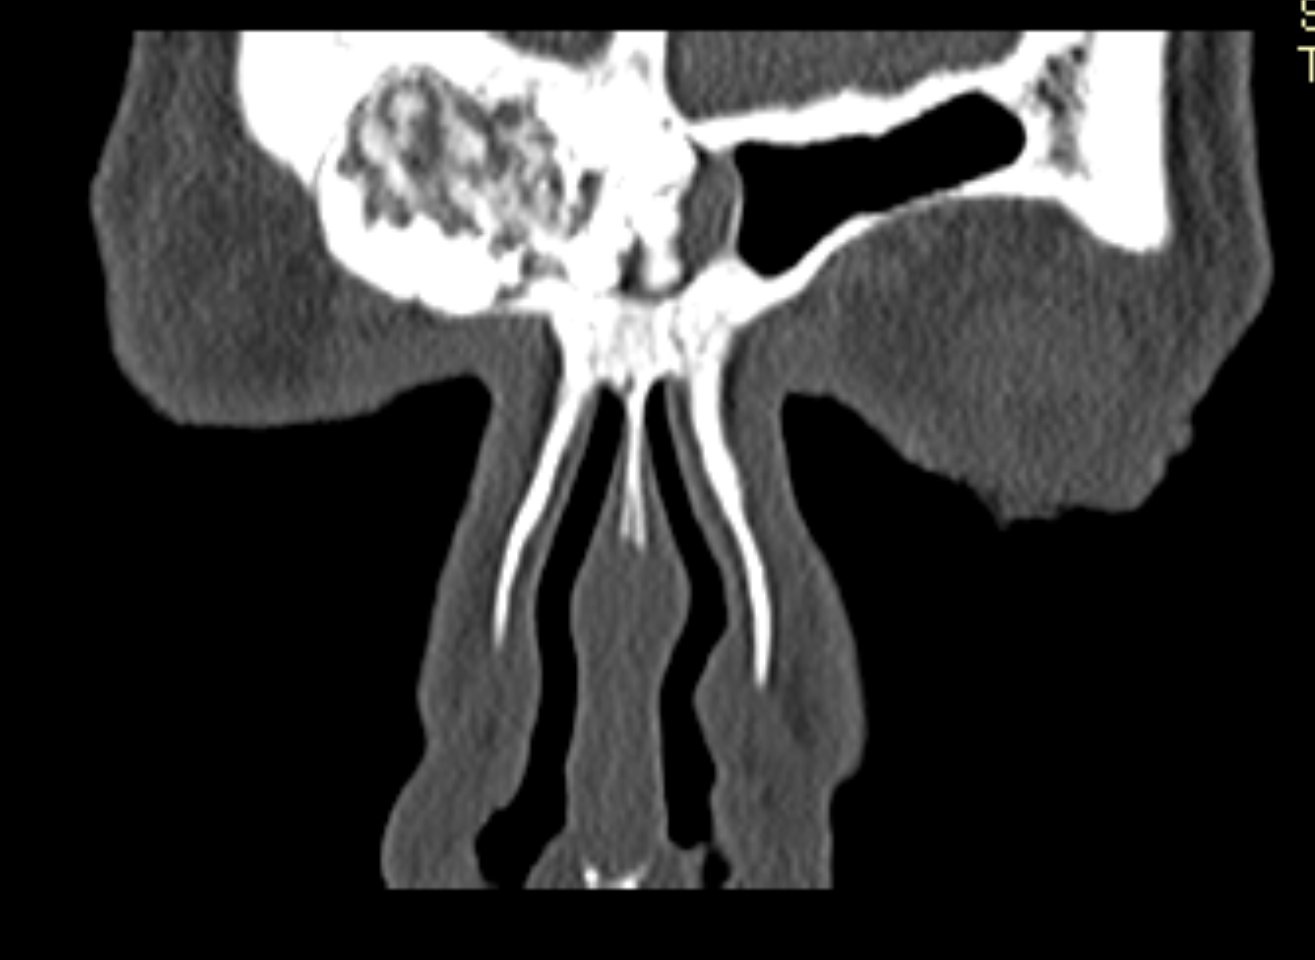

Examenul clinic ORL și examenele imagistice complementare (CT, RMN sinusuri paranazale) pun în evidență o formațiune tumorală osteogenică a sinusului frontal drept, protruzivă în unghiul supero-intern al orbitei, extinsă medial către sinusul frontal stâng.

- Se expune formațiunea tumorală osteomatoasă care ocupă în totalitate cavitatea sinusală frontală dreaptă, se extinde către sinusul frontal controlateral și către orbita dreaptă, creând presiune pe atmosfera celulo-grasoasă periorbitară la nivelul unghiului supero-intern OD. Formațiunea este intens aderentă la nivelul peretelui sinusal postero-superior. Aceasta prezintă două zone de consistență diferită.